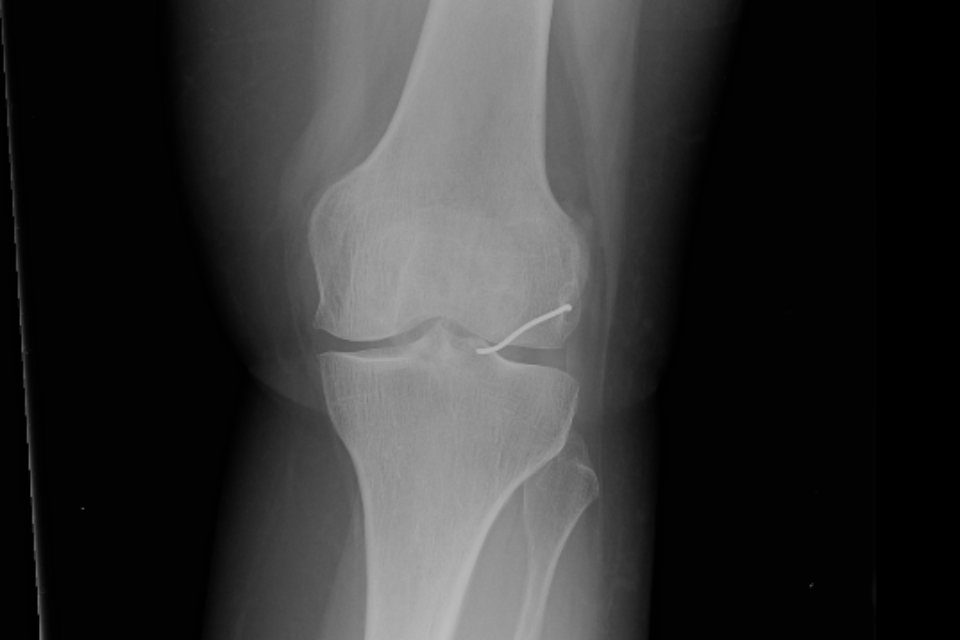

כעבור כשנתיים, ולאחר שספגה מהלומה באזור הברך, החלה האישה לסבול מכאבים עזים ונבדקה על ידי אורתופד. זה שלח אותה לצילומי רנטגן, וגילה, למרבה ההפתעה, כי בברך ישנה פיסת מתכת, והיא זו שככל הנראה גרמה לכאבים. האישה הופנתה לניתוח, שלישי במספר, ובמהלכו הוצא מברכה תיל מתכת באורך 3.5 ס"מ.